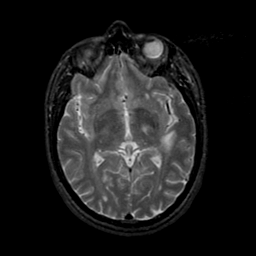

MR Study #21, November 3, 1991 -- Slice #24